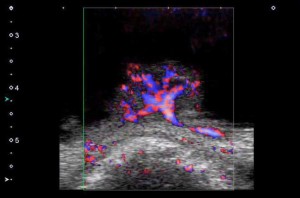

悪性リンパ腫(カラー表示モード)

今回受賞したSMIは、同社超音波診断システムのAplio™ シリーズに搭載可能な技術*で、組織の動きの速度に近いような低流速の血流を、高フレームレートに高分解能で表示することが可能。

SMIではモーションアーティファクト特有の特徴を解析し、臨床上必要な情報を効果的に取り出すことに成功した。SMIは、造影剤の適用されない場合でも、低流速検出能に優れた血流イメージングを提供でき、造影剤を使用すれば更に微細な血流の観察ができるので、がんや腫瘍、関節リウマチなどの早期診断や治療方針の決定などに大きく貢献することが可能となる。

今回受賞したSMIは、同社超音波診断システムのAplio™ シリーズに搭載可能な技術*で、組織の動きの速度に近いような低流速の血流を、高フレームレートに高分解能で表示することが可能。

SMIではモーションアーティファクト特有の特徴を解析し、臨床上必要な情報を効果的に取り出すことに成功した。SMIは、造影剤の適用されない場合でも、低流速検出能に優れた血流イメージングを提供でき、造影剤を使用すれば更に微細な血流の観察ができるので、がんや腫瘍、関節リウマチなどの早期診断や治療方針の決定などに大きく貢献することが可能となる。